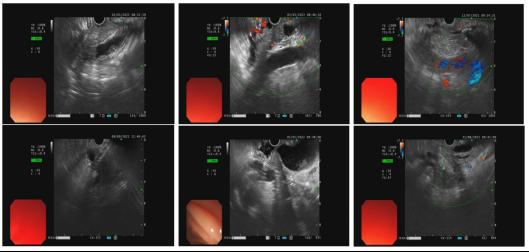

消化内科编制床位141张,年门诊平均就诊量约十万余人次,出院约6000余人次,内镜诊疗60000余人次,手术或治疗4千余例。我院地处川东北地区,长期收治不明原因腹水、不明原因消化道出血、不明原因腹痛、急性重症胰腺炎、肝硬化伴严重并发症及消化道大出血等疑难危急重症病人。作为川东北地区消化系统内科治疗的标杆,消化内科一直致力于示范和推广高水准的消化道诊疗技术,为提高诊疗技术,为广大患者提供更好的服务,我科购进了奥林巴斯小探头超声内镜、纵轴线阵扫描超声胃镜、奥林巴斯290色素放大内镜(NBI)、十二指肠镜、富士7000放大内镜、富士双气囊小肠镜等内镜下诊疗的高端设备。消化内科极其重视消化道肿瘤的早诊早治及消化内镜下一系列医疗技术,开展了EMR、 ESD、STER、POEM、EUS及内镜下止血等手术。同时,还大力开展消化放射介入治疗如ERCP等多项介入技术。消化内科联合急诊医学科、介入科、普外科等多科建立危险性消化道出血 MDT 团队,建立“危险性上消化道出血救治区域中心”,7×24 小时绿色通道,提供全面、优质诊疗方案,缩短危险性消化道出血急诊救治时间,大大提高了患者生存率。在临床工作中努力深化亚专科和各专业组建设,各专业组通过进修学习及各类学术交流、病例研讨等活动,不断提升团队整体实力,为患者提供更精准、更专业的医疗服务,努力在医学亚专业领域内实现新的突破与飞跃。

EUS超声内镜

EUS-FNA超声穿刺

6. 胰腺及腹盆腔占位病灶的超声内镜检查。